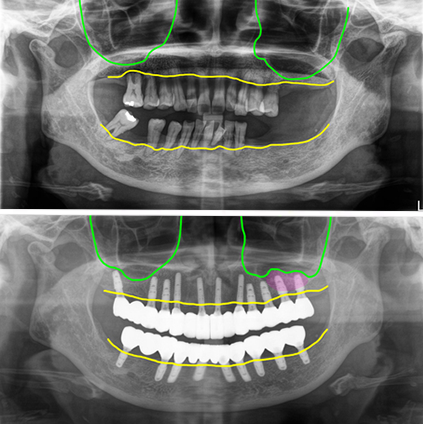

오늘 설명해 드릴 사례는 50대 여성 환자로 치주염(잇몸질환)이 심해 치조골이 모두 녹아서 치아들이 모두 흔들려 전체임플란트로 치료한 경우입니다.

치아들이 많이 남아있지만 겉으로 보기에는 그냥 치아가 멀쩡해 보이지만 사실상은 치조골이 모두 녹아서 치아들이 많이 흔들려서 치아의 기능을 제대로 할 수 없는 상태였습니다.

모두 치주염 말기에 해당해 치아를 발치하고 임플란트 치료를 진행하기로 결정을 했습니다. 상악 우측부에는 뼈가 있는 부위를 이용해서 식립을 하기로 했고, 좌측부에는 뼈가 너무 많이 없어서 상악동 윈도우 뼈이식을 하면서 식립을 하기로 했습니다.

상악 우측 어금니 부위에는 염증이 심해서 뼈가 많이 녹아있는 부분은 피해서 식립을 했고, 좌측 어금니 부위는 상악동 윈도우 뼈이식을 하면서 임플란트를 식립했어요.

발치를 하면서 뼈이식과 동시에 임플란트를 식립했고, 아래는 9개를 식립했습니다. 수술당일에 위쪽에 2개는 잇몸 속에 넣어두고 나머지의 임플란트는 지대주를 연결해서 임시치아를 제작해서 끼워 드렸습니다.

전체 내원 4회 (수술, 실밥, 스캔, 세팅) 치료기간 6개월에 모든 치료를 완료하셨습니다. 위쪽 왼쪽 상악동 윈도우 부분은 초기고정이 약해서 수술시에 잇몸 속에 임플란트를 넣어두었어요.

그리고 최종 보철을 할 때 절개를 해서 스캔바디를 끼운 후 촬영을 하고 2주 뒤에 최종보철을 세팅했습니다. 일반적으로 상악동에 윈도우 방식으로 대량의 뼈를 넣는 경우는 6개월 정도 기다리게 됩니다.